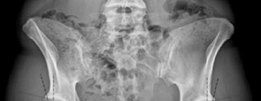

A 20-year-old man is brought to the emergency department following a high-speed road traffic accident in whic…

A 29-year-old man is brought into the emergency department after falling off his motorcycle in wet weather. H…